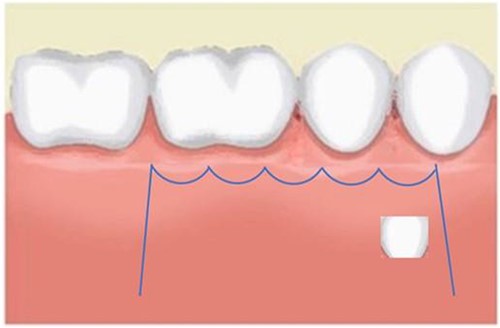

In this context, a buccal approach using a Neumann full-thickness flap was preferred (Fig. 4). When a buccal approach is planned, then the location of the mental nerve must be identified to avoid any post-operative sensory problems. The most challenging part is to exercise extreme caution during Ostectomy to avoid damage to the adjacent tooth roots.